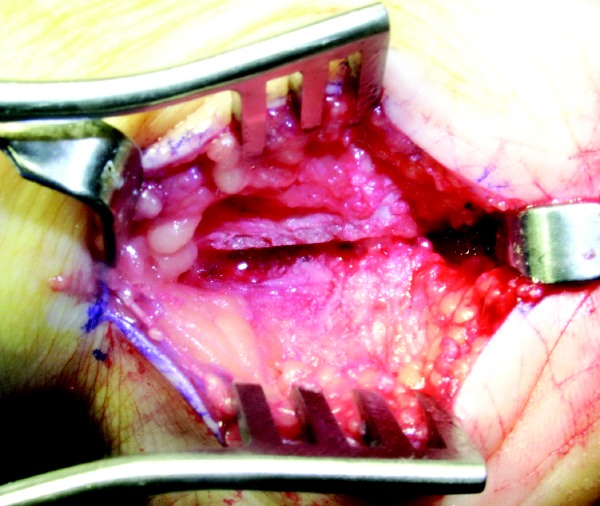

One should begin by placing the patient in the supine position on the operating table with a bump under the ipsilateral hip, placing the knee in the frontal plane to allow access to the lateral and medial hindfoot if medial tendon procedures are indicated. One may use spinal or general anesthesia. Prep the leg to the knee and drape the limb so you may access the posterior leg if a gastrocnemius recession or Achilles tendon lengthening is required. Place the incision for the PCDO on the posterior lateral aspect of the heel, beginning at a point approximately 2 cm anterior to the Achilles tendon and 1 cm posterior to the tip of the lateral malleolus. Extend the incision at a 45 degree angle toward the weightbearing surface in an anterior distal direction to a point just inferior to the calcaneal border. The incision remains posterior to the peroneal tendons. Incise the periosteum in the same fashion as the skin incision. Proceed with subperiosteal dissection to facilitate access for the sagittal saw. Dorsal dissection should reach just posterior to the posterior facet of the subtalar joint and inferiorly just anterior to the plantar tubercle. Hold the blade of the saw perpendicular to the lateral surface of the calcaneus and perform the osteotomy from lateral to medial. Use both hands to control the depth of the saw when approaching the medial cortex. Alternatively, you may use an osteotome to cut through or break the medial cortex. Place an osteotome within the osteotomy and stretch the medial periosteum. One may also utilize a lamina spreader to open and close the osteotomy completely, and stretch the medial periosteum. This maneuver will mobilize the tuber segment of the calcaneus and allow easy medial translation. Proceed to displace the posterior tuber medially and obtain provisional fixation with a 0.062 Kirschner wire or the guide wires for cannulated screw fixation. Hold the foot in plantarflexion during displacement in order to relax the inferior muscles, Achilles tendon and plantar fascia. This avoids sagittal plane displacement and allows for easy medial manipulation of the posterior segment. Translate the calcaneus approximately 1 cm medial. One should obtain a calcaneal axial view to ensure that you have achieved adequate correction. Achieve final fixation with one or two large diameter compression screws, and do not violate the subtalar joint. Osteosynthesis should be performed percutaneously under image intensification. One may choose to perform an osteoplasty of the remaining cortical shelf to avoid prominence. This will eliminate tension on the wound and avoid dehiscence. Adolescents with an open growth plate will require two smooth 5/64 in. or 7/64 in. Steinman pins, in lieu of screws, for final fixation. Surgeons may place these screws percutaneously or they may be buried. The incision for the Evans anterior calcaneal osteotomy is oblique or longitudinal, and made just distal to the sinus tarsi and 1 to 1.5 cm proximal to the calcaneocuboid joint (CCJ). Sometimes this can be deceiving if the plantar fat pad is laterally displaced. One must ensure careful dissection and preservation of the peroneal tendons and the sural nerve. It is important to identify the CCJ so one can avoid dissecting the periarticular structures that provide stability to this joint. Surgeons should perform the osteotomy approximately 1 cm proximal to the CCJ. Proceed to incise the periosteum in a vertical fashion. Avoid extensive plantar dissection and do not dissect the periarticular ligaments of the CCJ. This will prevent disruption of the long plantar ligament (LPL), which can result in an unstable distal segment following the osteotomy. This is not an uncommon radiographic finding following this procedure. Keep in mind that this still can occur depending on the size of the bone graft and stretch on the LPL. Ensure that the sagittal saw blade is angled just anterior to approximate the area in between the anterior and middle facets. One would also keep the osteotomy perpendicular to the weightbearing surface. Use caution when approaching the medial cortex. Exiting too far medially may compromise vital medial structures. It can sometimes be difficult to appreciate the medial cortex in this subchondral region of the calcaneus. One may use an osteotome to finish the osteotomy.